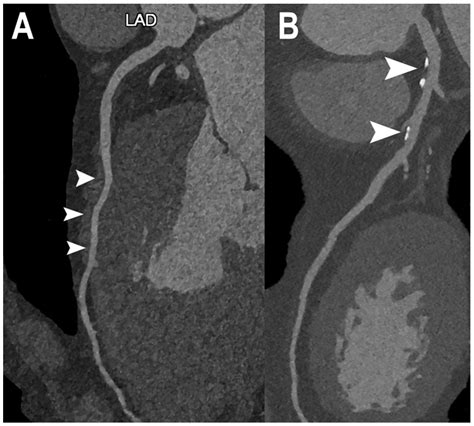

At its core, a Cardiac CT scan is an imaging test that allows cardiologists and radiologists to see if your coronary arteries are narrowed or blocked by plaque buildup—a condition known as atherosclerosis. Unlike traditional stress tests, which provide functional information about how your heart handles exertion, a cardiac CT provides anatomical information. It captures images of the heart while it is beating, using sophisticated gating technology to synchronize the image acquisition with your heart rhythm.

This technology is particularly effective at identifying early-stage heart disease before symptoms manifest. By visualizing the calcified and non-calcified plaque within the arterial walls, physicians can initiate preventative treatments far earlier than previously possible.

Once the scan is complete, the images are sent to a radiologist or a specialized cardiologist who analyzes the anatomy of your coronary arteries. They will look for the presence and extent of plaque, the degree of arterial narrowing (stenosis), and the presence of any calcium deposits. You will receive a formal report, and your primary doctor will discuss the findings with you to determine the next steps in your care plan. Depending on the findings, these steps may include lifestyle modifications, cholesterol-lowering medication, or further diagnostic testing.